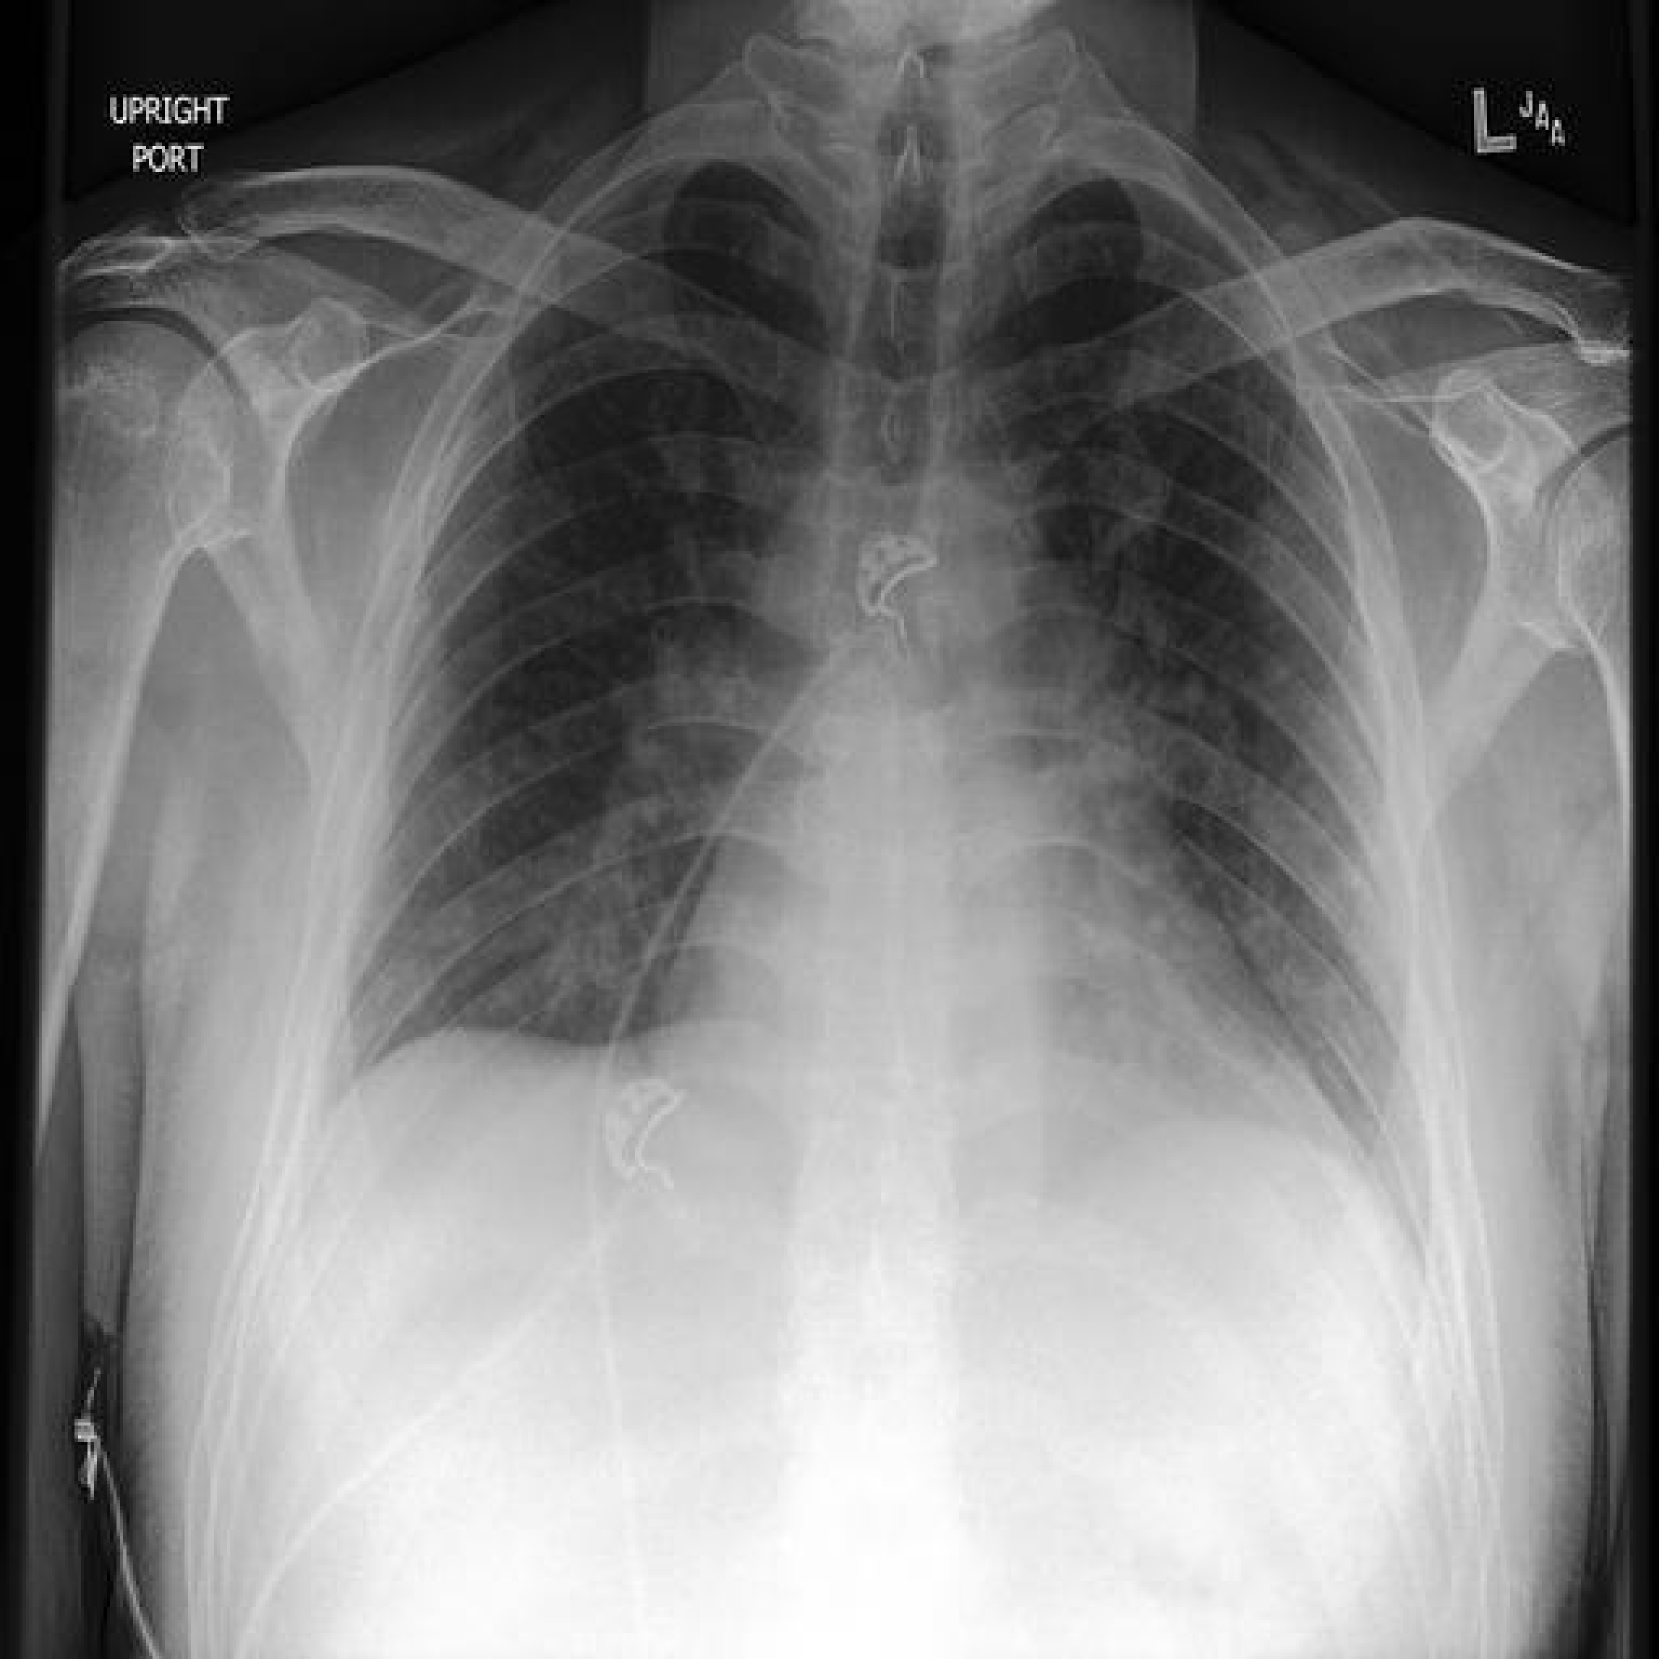

To generate CF medical images with language guidance, PRISM adopts the image-editing technique used in LANCE [Prabhu et al.(2023)Prabhu, Yenamandra, Chattopadhyay, and Hoffman], which combines Null-text inversion [Mokady et al.(2023)Mokady, Hertz, Aberman, Pritch, and Cohen-Or] with Prompt-to-prompt [Hertz et al.(2022)Hertz, Mokady, Tenenbaum, Aberman, Pritch, and Cohen-Or] attention manipulation. Algorithm A.1 presents the detailed pseudo-code outlining the three key steps involved in PRISM’s image editing process: (i) image inversion, (ii) image editing, and (iii) quality evaluation of the generated image.

Image Inversion: In the inversion stage, the objective is to recover a latent representation of the original image and optimize unconditional embeddings to ensure accurate reconstruction. First, the original image I\textorigsubscript𝐼\text𝑜𝑟𝑖𝑔I_{\text{orig}}italic_I start_POSTSUBSCRIPT italic_o italic_r italic_i italic_g end_POSTSUBSCRIPT is encoded into the latent space as zTsubscript𝑧𝑇z_{T}italic_z start_POSTSUBSCRIPT italic_T end_POSTSUBSCRIPT using an image encoder EIsubscript𝐸𝐼E_{I}italic_E start_POSTSUBSCRIPT italic_I end_POSTSUBSCRIPT. A deterministic DDIM reverse diffusion then produces the latent sequence {zT,zT1,,z0}subscript𝑧𝑇subscript𝑧𝑇1subscript𝑧0\{z_{T},z_{T-1},\ldots,z_{0}\}{ italic_z start_POSTSUBSCRIPT italic_T end_POSTSUBSCRIPT , italic_z start_POSTSUBSCRIPT italic_T - 1 end_POSTSUBSCRIPT , … , italic_z start_POSTSUBSCRIPT 0 end_POSTSUBSCRIPT }.

Unconditional embeddings E\textuncondsubscript𝐸\text𝑢𝑛𝑐𝑜𝑛𝑑E_{\text{uncond}}italic_E start_POSTSUBSCRIPT italic_u italic_n italic_c italic_o italic_n italic_d end_POSTSUBSCRIPT are randomly initialized, while conditional embeddings E\textcondsubscript𝐸\text𝑐𝑜𝑛𝑑E_{\text{cond}}italic_E start_POSTSUBSCRIPT italic_c italic_o italic_n italic_d end_POSTSUBSCRIPT are derived from the original prompt P\textorigsubscript𝑃\text𝑜𝑟𝑖𝑔P_{\text{orig}}italic_P start_POSTSUBSCRIPT italic_o italic_r italic_i italic_g end_POSTSUBSCRIPT. For each diffusion step (from t=T𝑡𝑇t=Titalic_t = italic_T to t=1𝑡1t=1italic_t = 1), a predicted latent z^t1subscript^𝑧𝑡1\hat{z}_{t-1}over^ start_ARG italic_z end_ARG start_POSTSUBSCRIPT italic_t - 1 end_POSTSUBSCRIPT is computed using E\textcondsubscript𝐸\text𝑐𝑜𝑛𝑑E_{\text{cond}}italic_E start_POSTSUBSCRIPT italic_c italic_o italic_n italic_d end_POSTSUBSCRIPT and the current E\textuncondsubscript𝐸\text𝑢𝑛𝑐𝑜𝑛𝑑E_{\text{uncond}}italic_E start_POSTSUBSCRIPT italic_u italic_n italic_c italic_o italic_n italic_d end_POSTSUBSCRIPT. The mean squared error, =z^t1zt12superscriptnormsubscript^𝑧𝑡1subscript𝑧𝑡12\mathcal{L}=\|\hat{z}_{t-1}-z_{t-1}\|^{2}caligraphic_L = ∥ over^ start_ARG italic_z end_ARG start_POSTSUBSCRIPT italic_t - 1 end_POSTSUBSCRIPT - italic_z start_POSTSUBSCRIPT italic_t - 1 end_POSTSUBSCRIPT ∥ start_POSTSUPERSCRIPT 2 end_POSTSUPERSCRIPT, is minimized via gradient descent to update E\textuncondsubscript𝐸\text𝑢𝑛𝑐𝑜𝑛𝑑E_{\text{uncond}}italic_E start_POSTSUBSCRIPT italic_u italic_n italic_c italic_o italic_n italic_d end_POSTSUBSCRIPT. This null-text inversion process aligns the latent representation with the original image, preserving its structure and style for accurate reconstruction and reliable editing. Figure 5 shows the original and inverted images, with many details preserved during generation. Notably, the model struggles with the small text found within the images, which we further discuss in Appendix I. When the original and inverted images are passed through the state-of-the-art classifier, the changes in multi-class logit values are close to zero. This confirms that the inversion process maintains relevant details needed for accurate image classification.

Refer to caption

Figure 5: The inversion quality of the proposed generative model.

Although our method is capable of synthesizing high-resolution images (512×512512512512\times 512512 × 512), it faces difficulties in reproducing the small text written in the corner of radiographs (Fig 14) in both the inverted and CF images. This inability of Stable Diffusion to resolve fine text is a known phenomena and is also seen in natural images [Mokady et al.(2023)Mokady, Hertz, Aberman, Pritch, and Cohen-Or].